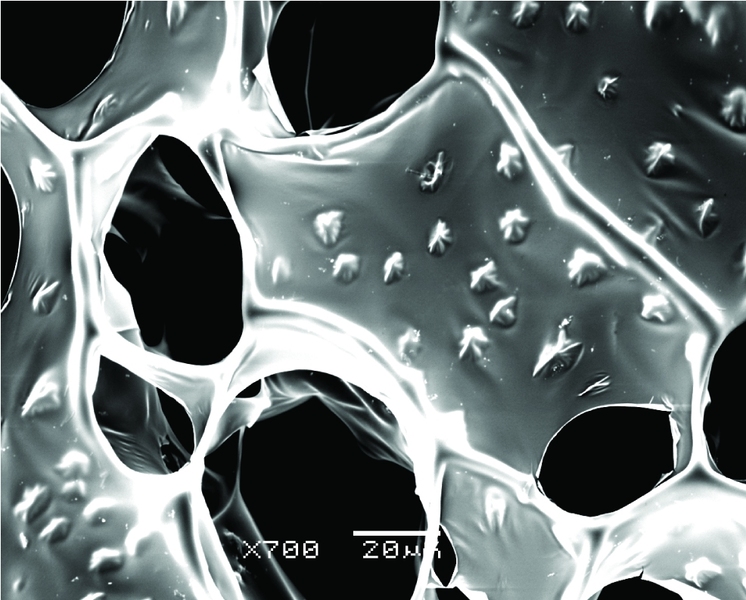

To build new tissue, biological engineers typically use miniature scaffolds resembling porous sponges to organize cells into functional shapes as they grow. Traditionally, however, these scaffolds have been made from materials with poor electrical conductivity — and for cardiac cells, which rely on electrical signals to coordinate their contraction, that’s a big problem.

The team took as their base material alginate, an organic gum-like substance that is often used for tissue scaffolds. They mixed the alginate with a solution containing gold nanowires to create a composite scaffold with billions of the tiny metal structures running through it.